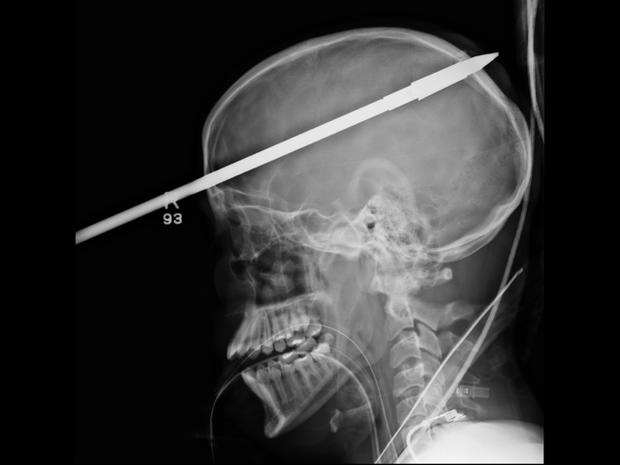

16-year-old Yasser Lopez of Miami was injured when a spear gun his friend was holding accidentally discharged, causing a spear more than three-feet long to impale his skull and brain. Amazingly the teen survived, and was even able to speak to doctors throughout the whole ordeal.